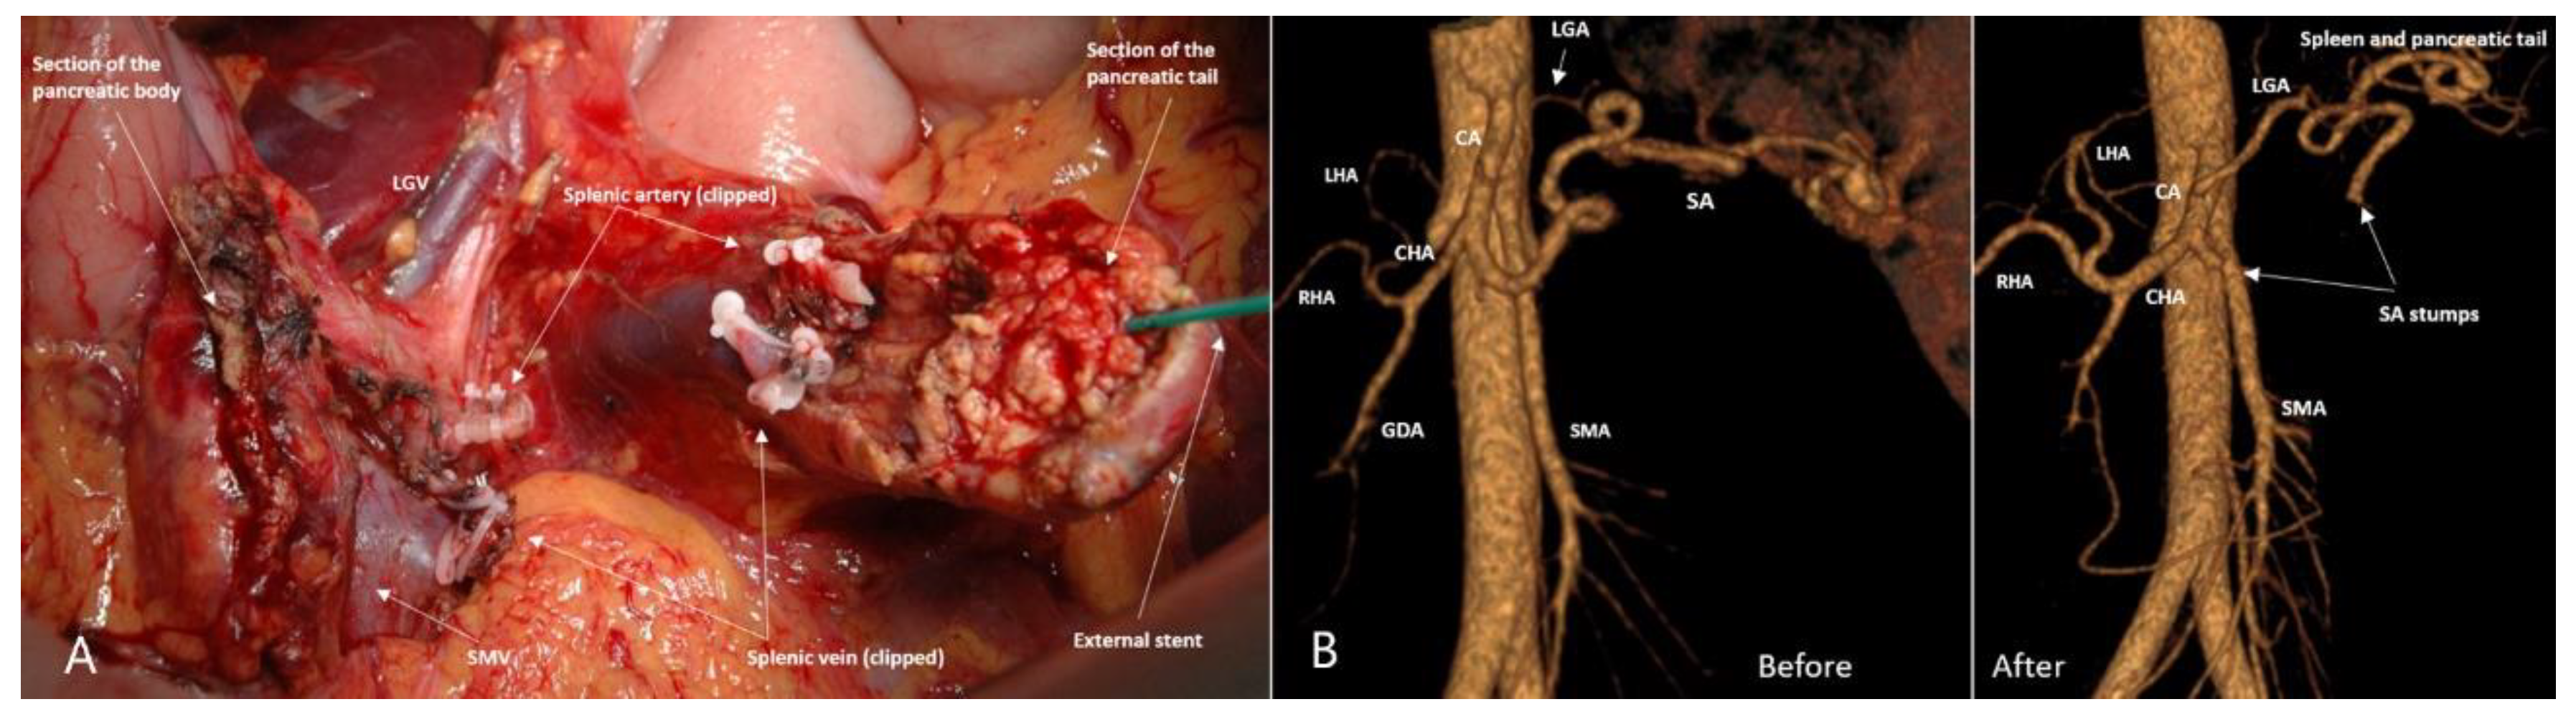

3.3. Spleen-Preserving Pancreatectomies with Resection of the Splenic Vessels, Other than Distal Resections

3.4. Spleen-Preserving Pancreatectomies with Resection of the Splenic Artery (Vessels) for Border Line Resectable and Locally Advanced Pancreatic Head Cancers